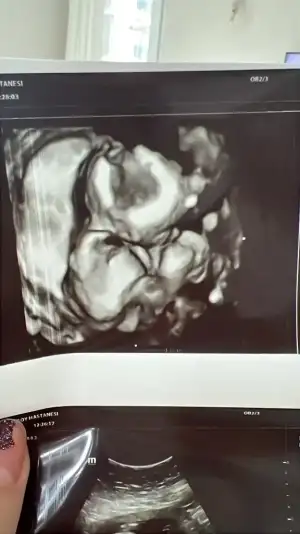

Uzun zamandan sonra bugün kontole gittim maltepe ersoy hastanesine yeni bi dr gelmiş osman aydın diye iyi biri gibi bi çok şeyi açıkladı tüm sorularıma cevap verdi. Hatta bebiş yüzünü bi türlü dönmedi poz versin diye bile baya uğraştı ama anca bu oldu

250 gram olmuş minnoşum ayakları ağzında duruyordu

bi türlü yüzünü göstermedi minnoşum